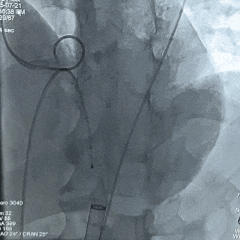

手术过程

左冠造影检查

20mm球囊扩张,无腰无漏,球囊轻微滑动

TF23瓣膜0位初始释放

瓣膜第一次展开造影评估,位置偏浅,回收调整

第二次释放造影评估

瓣膜深度可,展开良好,无瓣周漏

瓣膜解锁后造影评估

瓣膜深度合适形态良好,冠脉灌注良好,无瓣周漏

最终多角度观察瓣膜形态,瓣膜展开良好

超声测量流速1.5m/s,手术结束